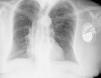

Mulher de 74 anos, com colocação de pacemaker definitivo (VDD) há cerca de 2 anos por BAV de 3.° grau, sem intercorrências, recorre à consulta de pacemaker de rotina. Não apresentava qualquer sintomatologia. Foi detetada disfunção do pacemaker (undersensing e falhas de captura), tendo-se realizado radiograma do tórax em incidência póstero-anterior que mostrou projeção extracardíaca da extremidade do eletrocateter (Figura 1). A doente foi submetida a tomografia computorizada (TC) torácica, com aquisição espiral multidetetores (TCMD 16 cortes) e reconstruções multiplanares 2D (RMP) e 3D que confirmou a localização extracardíaca da extremidade do eletrocateter, com topografia intratorácica justadiafragmática (Figuras 2–4).